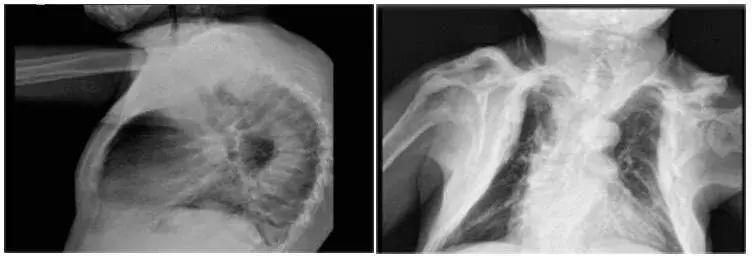

不仅是手的骨骼,他全身其他多处骨骼呈现了类似这样的骨质溶解,导致他的身高缩短了22厘米。也就是说,本来1米7的个子,缩短到不足1米5。